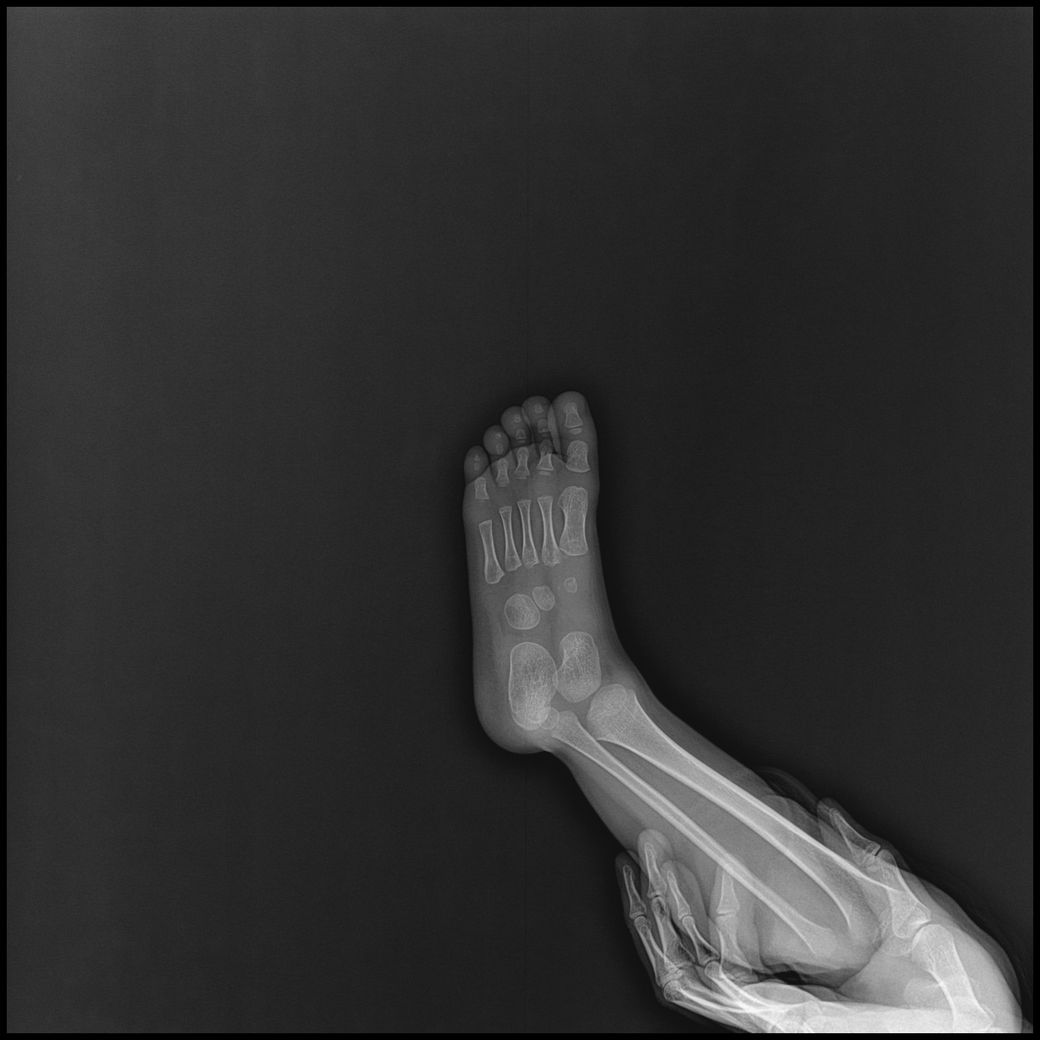

아기 손발 엑스레이를 찍게되었는데요.

손목, 발목까지 6-8장 찍기로 안내받았으나,

고관절,복부일부,생식기등 민감부위등이 추가로 촬영되었고

발도 다리가 다 찍혔고 총 19장이 찍혔습니다.

- 몸통일부+손같이찍힘 : 6장

- 손부터 팔꿈치까지 : 3장

- 발~다리사진 : 10장

• 1번 째 사진